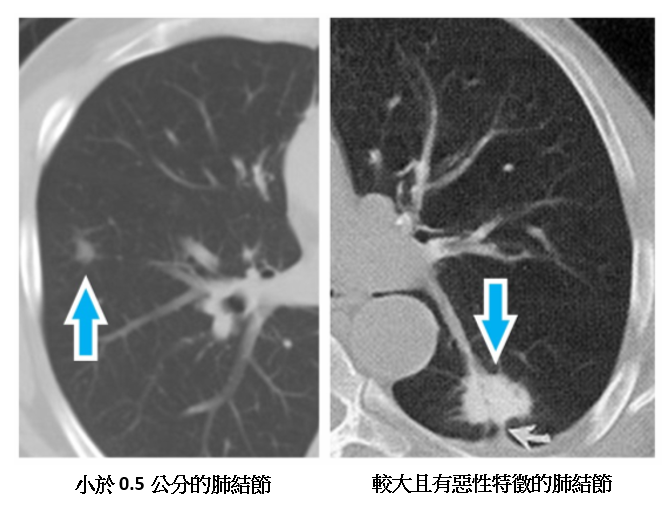

是什麼樣的考量因素,讓她和醫師決定這麼做?澄清醫院中港院區胸腔外科主治醫師杜承哲說首要原則就是「抓大放小、除惡安良」。從患者的肺部電腦斷層影像可以看出,有2個結節為1.2公分,而且是典型的毛玻璃樣病變,有明顯的惡性特徵;其餘12個皆小於0.5公分,幾乎沒有惡性特徵。

▲ 患者的肺部電腦斷層影像

小於0.5公分肺結節 惡性機率極低

一般認為,小於0.5公分的肺結節,要是惡性的機率是非常非常低,在未來要變化成惡性或是轉移的機會也不高。除了大小之外,肺結節的外觀特徵及變化,也是非常重要的參考依據──有些患者身上的腫瘤,也許只有1公分,但是惡性的特徵非常明顯,就應該要盡早手術;有些患者的腫瘤是屬於惡性特徵很低的,要等到觀察有變化,才需要接受手術。